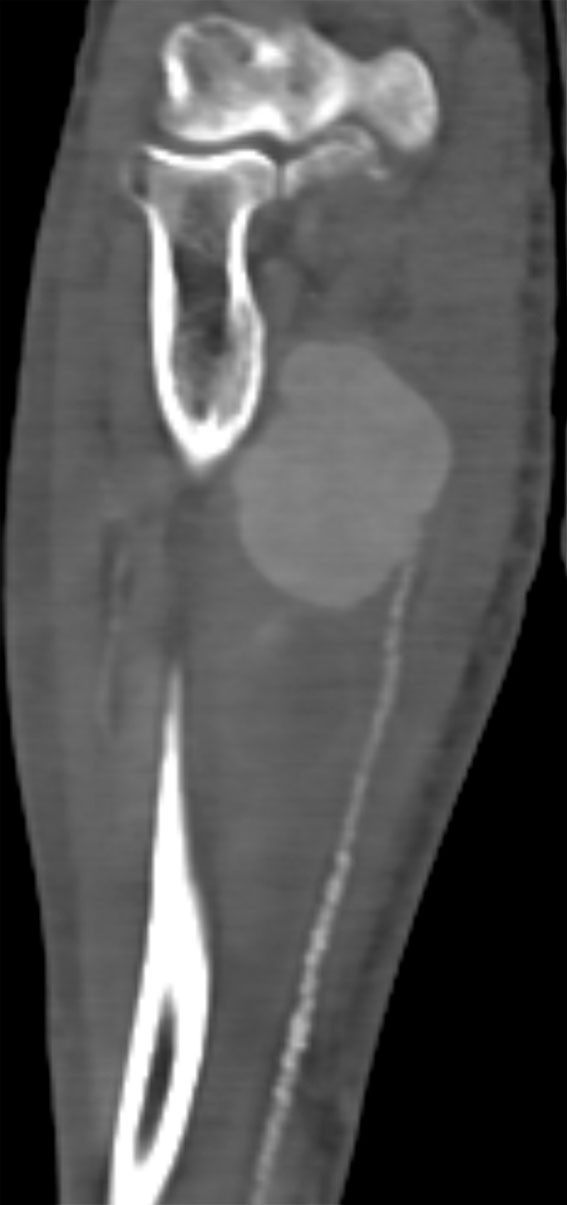

Twelve days after admission, the patient noticed a painful swelling in his right forearm. Ultrasound revealed an aneurysm on the ulnar artery. CT angiography taken the same day confirmed the ultrasound findings and revealed an aneurysm measuring 7.5 × 4 cm (Figure 1). There were numerous atherosclerotic changes distal to the aneurysm. Clinical examination found good circulation to the hand on occlusion of the ulnar artery.